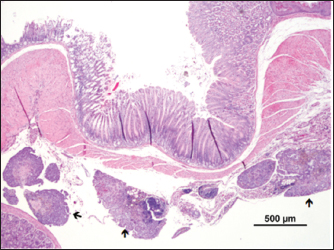

The mass presented areas of epidermal differentiation with laminated keratin and sebaceous glands. Cell differentiation into digestive and respiratory epithelium, bone, cartilage, and vast areas of differentiation into nervous tissue were also present (Figs. 37). Moreover, the nervous tissue presented focal areas of ependymoma. Epithelial areas with hypercellularity, cell atypia, stromal microinvasion, hemorrhages, and necrosis were also observed. Metastatic epithelial cells were detected invading the pancreas, the small intestine serosa, and the mesenterium. Therefore, the mass was classified as a malignant teratoma with abdominal carcinomatosis.

Fig. 7. Metastasis on gut serosa ( ) (H&E).